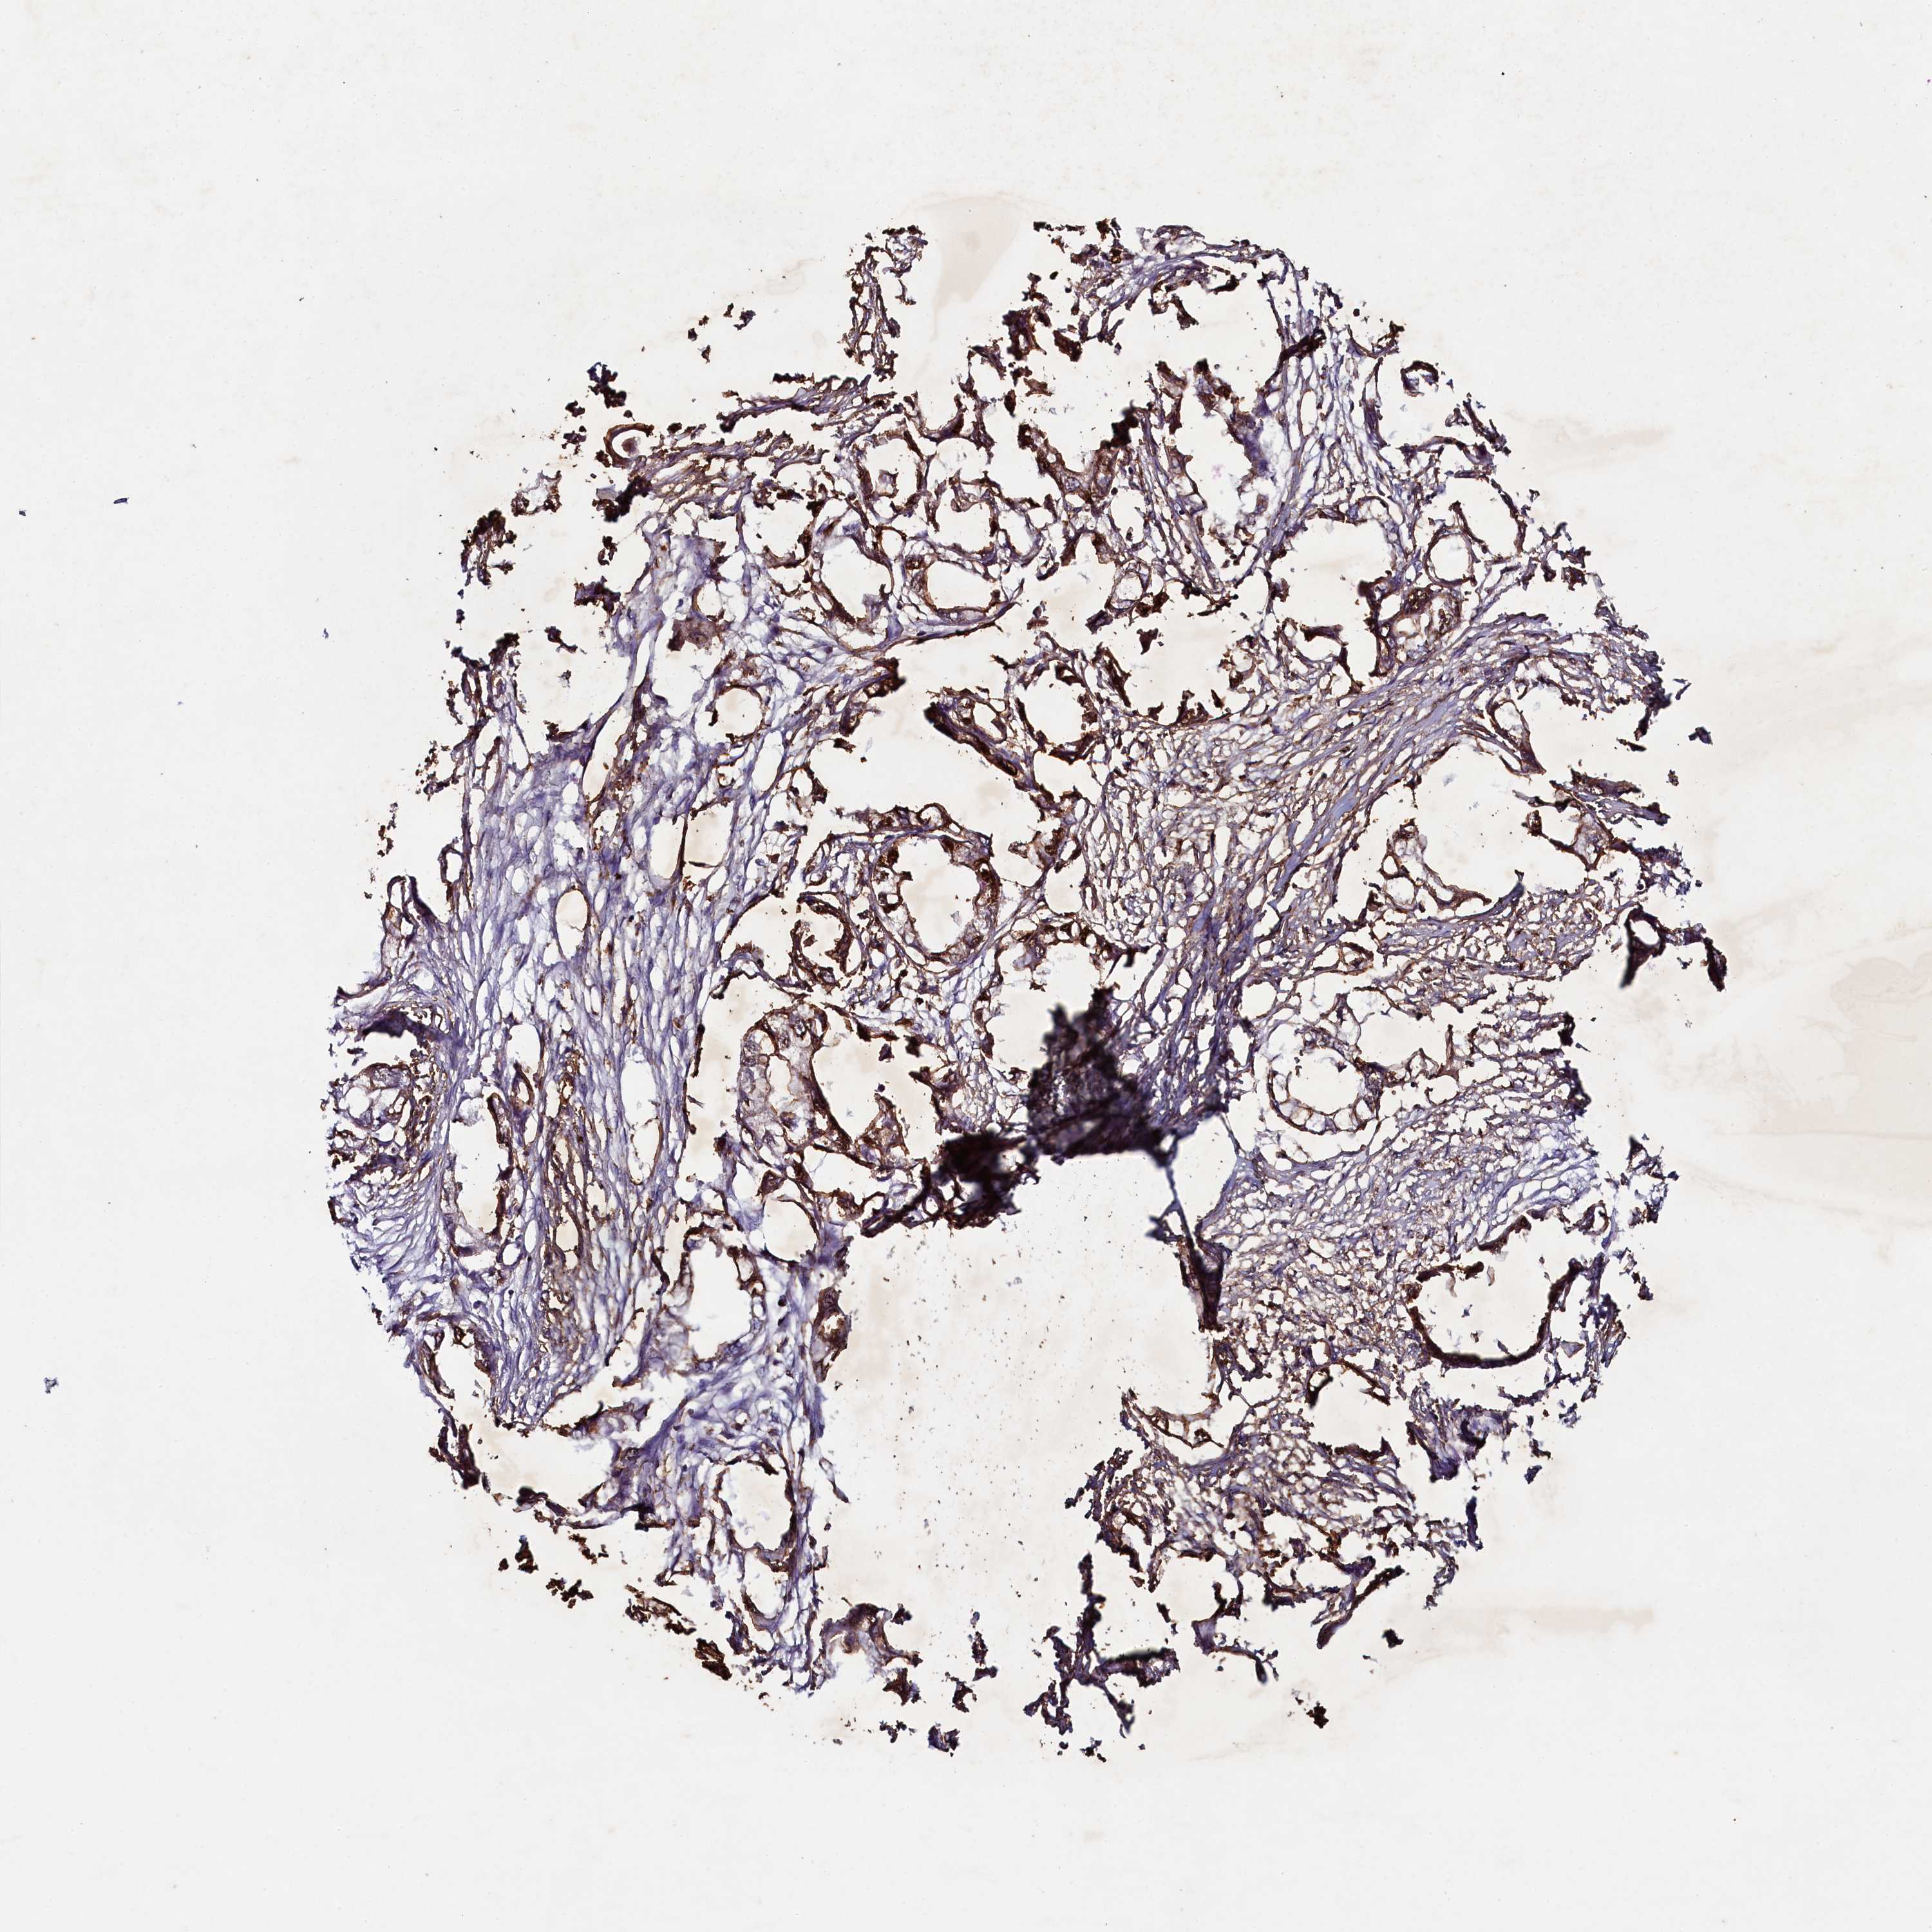

ENDOMETRIAL CANCER - Protein expressioni

A mouse-over function shows sample information and annotation data. Click on an image to view it in a full screen mode. Samples can be filtered based on level of antibody staining by selecting one or several of the following categories: high, medium, low and not detected. The assay and annotation is described here.

Note that samples used for immunohistochemistry by the Human Protein Atlas do not correspond to samples in the TCGA dataset.

Antibody stainingi

Antibody staining in the annotated cell types in the current human tissue is reported as not detected, low, medium, or high, based on conventional immunohistochemistry profiling in selected tissues. This score is based on the combination of the staining intensity and fraction of stained cells.

Each image is clickable and will lead to virtual microscopy that enables deeper exploration of all samples and also displays staining intensity scores, fraction scores and subcellular localization as well as patient and tissue information for each sample.